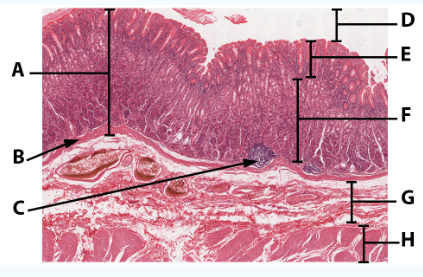

A

Mucosa

B

Muscularis mucosa

C

MALT

D

Lumen

E

Gastric pits: simple columnar epithelium

F

Gastric glands

G

Submucosa

H

Muscularis externa: oblique, circular, and longitudinal

area

Stomach